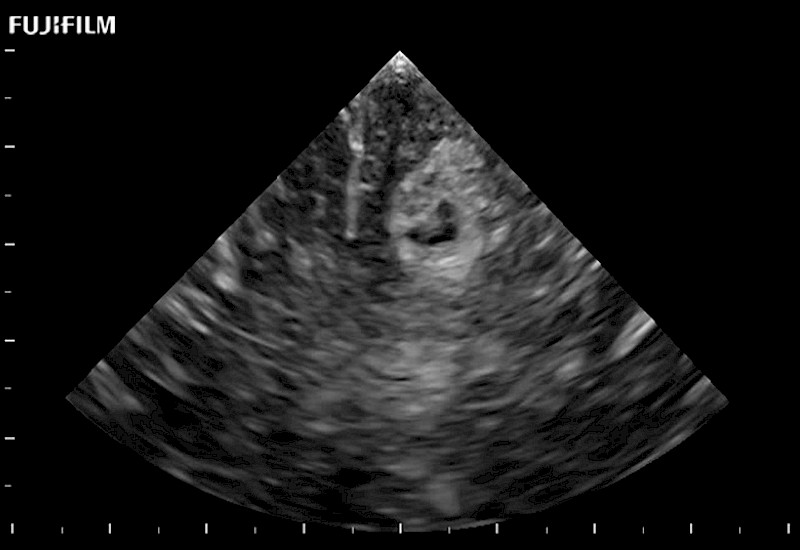

Tight curved (12mm) array transducer that is ideal for scanning during cranial guidance procedures.

The world's only phased array burr-hole transducer that is ideal for scanning during burr-hole guidance procedures.

Smaller footprint (20mm) curved array transducer that is ideal for scanning during cranial guidance procedures.

Exclusive 10mm side‐fire linear array transducer with 2.87mm diameter is ideal for real‐time visualization through and behind structures and instant, scalable definition of anatomy and vascularity including the ability to delineate and define tumor margins.